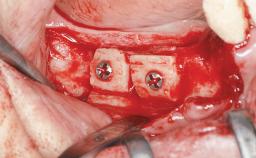

Guided Bone Regeneration (GBR) with a Particulated Autologous Graft and a ePTFE-Reinforced Membrane for Vertical Augmentation of a Single-Tooth Edentulous Space in the Esthetic Zone

A 47-year-old Caucasian woman with a single-tooth edentulous space at the site of the left maxillary canine was referred for treatment. She had undergone traumatic extraction of this impacted canine several months before referral. Her chief complaint was the dissatisfying appearance of her smile. The patient desired a stable and esthetic rehabilitation of the site. Her dental history showed no evidence of periodontal disease or bruxism. She had no systemic diseases, was not taking any medications, and did not smoke. The extraoral examination revealed a high lip line and an inadequate soft-tissue volume at the defective canine site. Large black triangles were visible between the canine and its adjacent teeth.

| Bone Augmentation | Staged|Vertical |

| Augmentation Materials | Autogenous chips|Membrane |

| Bone Volume | Deficient vertically or deficient vertically AND horizontally |